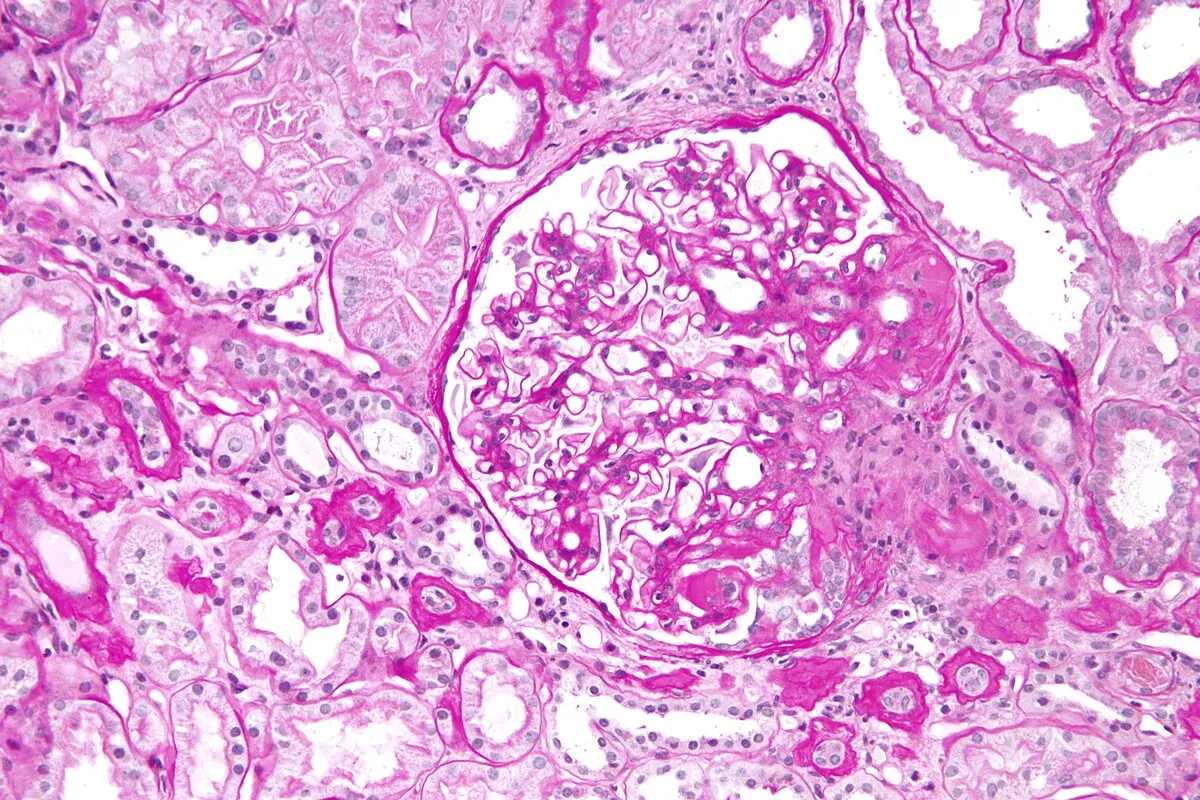

Ainda trata GESF do jeito antigo? Veja o novo algoritmo passo a passo! A abordagem da glomeruloesclerose segmentar e focal mudou — e muito. As classificações atuais vão além da histologia, integrando genética, etiologia e resposta terapêutica. Este post resume o novo algoritmo diagnóstico-terapêutico de forma prática, para você atualizar sua conduta em minutos.